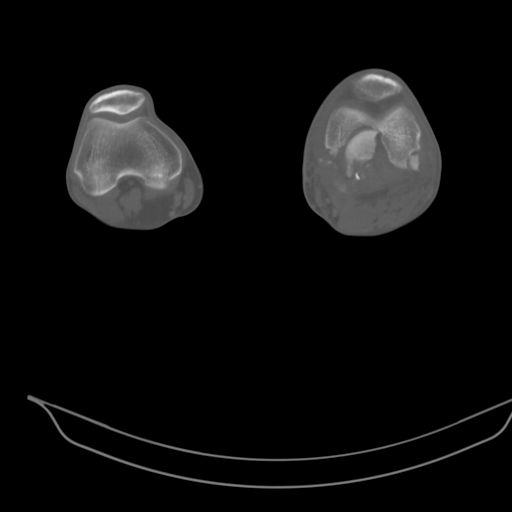

При внутрисуcтавных переломах трехмерные (3D) изображения, кроме красивого снимка, не дают полную информацию о состоянии отломков, самыми информативными являются корональные срезы на КТ и обычная длинная ренгенограмма конечности для сравнения оси конечности.

CT shows major bony fragments which are markedly rotated .With this amount of bony damage,you probably should attempt to get reasonably loooking knee with ORIF and thn if he needs a TKR due to pain a few years from now, then tleast you have something looking like a knee that you can replace rather than having to use revision knee for a primary TKR now. 4 weeks is not too long .what is the condition of soft tissues?

Фронтальные внутрисуставные переломы мыщельков бедра, так называемые Hoffa fracture, не частые, но встречающиеся переломы, в основном они связаны с травмой высокой энергией.

В зависимости от смещения рекомендуется сопоставление костных фрагментов с последующей жесткой фиксацией.

В вашем случае доступ будет медиальный, сопоставить развернутый медиальный мыщелок и фиксацию надо произвести в передне-заднем

направлении шурупами 4.5 мм в диаметре, углубив головку шурупов под хрящ, а поперечную фиксацию - межмыщелковыми шурупами. Желательно применить шурупы 6.3 мм в диаметре. Дополнительная Buttress technique пластина предотвратит перелом от скольжения.